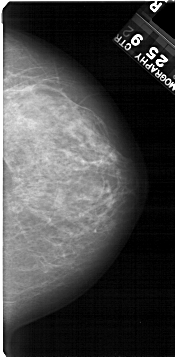

A_1368_1.RIGHT_CC

RIGHT_MLO LINES 5491 PIXELS_PER_LINE 3211 BITS_PER_PIXEL 12 RESOLUTION 43.5 NON_OVERLAY